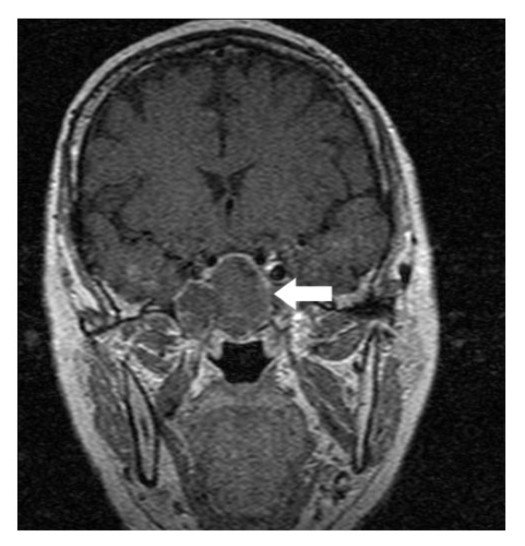

A 64-year-old lady presented to the outpatient department with complaints of headache and right eye blurring of vision for one month. Neurological examination revealed that bitemporal hemianopsia and impairment of visual acuity. Findings from fundus examination were within normal limits. Rest of the brain appeared unremarkable. Endocrine evaluation was normal. Results of renal function tests, liver function tests and haemogram test were within normal limits. A clinical diagnosis of non-secretory pituitary adenoma was made. Magnetic resonance imaging showed a well-circumscribed contrast-enhancing lesion in the sella (Figure 1, Figure 2). The patient underwent an endoscopic endonasal/transsfenoidal surgery in the supine position and total lesion resection was peformed. Intraoperatively, the lesion was found to be yellow colour, soft and avascular and it was removed totally until the sella turcica was visualized (Figure 3).In histopathologic examination septate hyphae were observed between inflammatory cells, Grocott staining is positive, but acid-fast stain for acid-fast bacilli (AFB) was negative. Histopathological findings suggest that infection of Actinomyces (Figure 4, Figure 5). We performed to patient consulted by patients to infectious diseases clinic. Patients underwent intravenous 6x2 gr ampicillin for four weeks.Then oral 4X500 mg amoxicillin treatment is planned a for at least 6 months. Patient did not have any deficits in the next six months.

Figure 2.White arrow shows on coronal section of MRI that a well-circumscribed contrast-enhancing lesion in the sella

Preoperative diagnosis of pituitary abcess is difficult because the presenting symptoms in these patients are similar to that in patients with pituitary adenomas 4. The most common symptoms are headache, vision disturbances and endocrinological abnormalities 5. Magnetic resonance imaging is the best imaging modality for sellar abscess and the features include a hypo- or iso-intense sellar mass on T1-weighted sequences and a hypointense mass on T2-weighted sequences pituitary abscesses may be divided into primary and secondary types. Primary pituitary abscesses occur within a previously healthy gland, while secondary abscesses arise within an existing lesion, such as an adenoma, craniopharyngioma, or Rathke's cleft cyst. Secondary abscesses share radiologic characteristics with the lesions from which they arise. The typical primary pituitary abscess gives the same or slightly lower signal than brain on T1-weighted images, and could be mistaken for a solid mass or presumed to represent a pituitary adenoma. Contrast-enhanced images are useful, demonstrating absence of central enhancement, suggesting a fluid or necrotic center 6.Actinomyces brain abscess is usually diagnosed based on the contrast enhancement on the periphery as in this case.Also MRI spectroscopy findings are the described in actinomyces infection 7, 8.